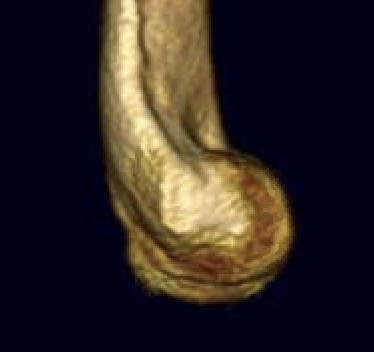

OTA / AO Classification

Type A: Extra-articular fracture

Type B: Partial articular fractures

Lateral condyle Medial condyle

Type C: Complete articular fractures

CT scan